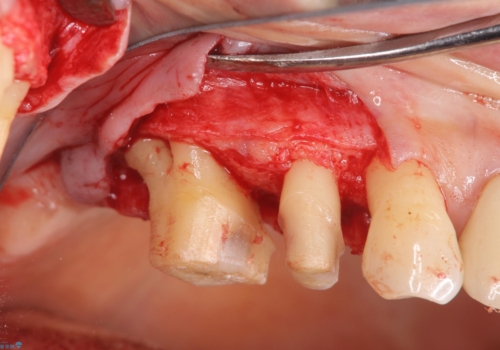

最後方臼歯は根尖部まで歯周病が進行しており、抜歯を行なったのち、残存歯は歯周外科を行なったのちオールセラミッククラウンにて修復治療を行なっています。

歯周外科を行う事により歯周ポケットを除去し予知性の高い治療を行うことができますが治療期間がかかります。